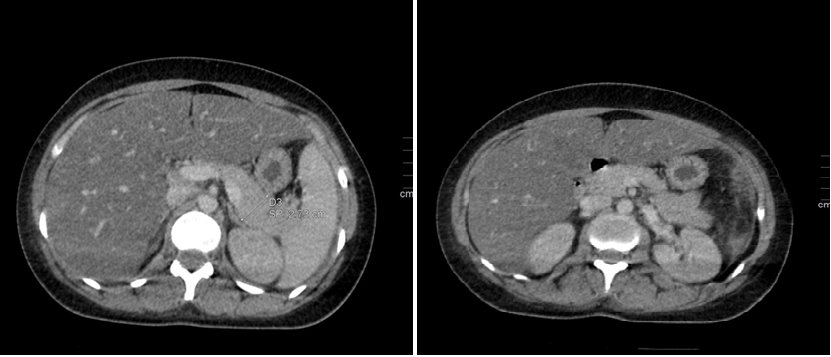

Anorectal Gastrointestinal Stromal Tumor: About a Rare Case Report and Review of Literature

Aouroud Hala, Jihane Rizkou, Khadija Krati

International Journal of Innovative Research in Medical Science·October 28, 2022